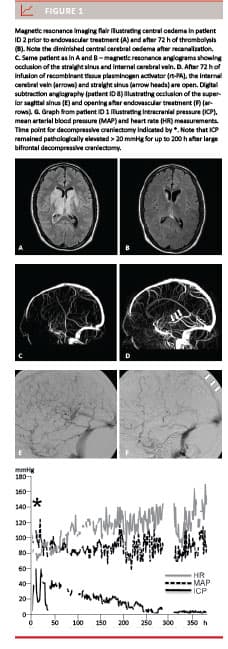

A total of nine patients were treated by endovascular therapy, eight females (89%) and one male. The average age was 21.1 year. The average time from initial symptoms and signs to diagnosis was five days (range 1-14 days). Eight (89%) complained of symptoms of increased intracranial pressure, i.e. headache and nausea as initial symptoms. Other symptoms were either focal neurological signs or unspecific. The initial diagnosis was based on cerebral CT in five cases (56%), on MRI in two (22%) cases and both in three cases (33%). Four (44%) had oedema in the central basal ganglia (Figure 1 A, B), four (44%) had minor haemorrhages/venous infarcts at the time of diagnosis and six (67%) patients had a general cerebral oedema and small cerebral haemorrhages at the time of diagnosis.

Thrombectomy was performed in six (67%) cases. In five of these cases (56%), this was followed by endovascular thrombolysis for 24 (one cases) or 72 h (four cases) until recanalization occurred. The remaining three cases were treated with thrombolysis alone. The patients were subjected to daily DSA within 72 h until recanalization was observed. In two cases, endovascular treatment resulted in full recanalization (22%) and in the remaining seven cases (78%) partial recanalization was obtained (Figure 1 C, D, E, F).

Five intubated and sedated patients were monitored with Camino ICP monitoring (56%, graphs from patient ID 1 shown in Figure 1 G). Four patients were treated with external ventricular drainage for ICP control (44%). In three patients, decompressive craniectomy was subsequently performed to obtain ICP control (33%). The ICP curves for those three patients showed a gradual decline in ICP to values below 20 mmHg over approximately 70 to 200 h after decompressive craniectomy. After obtaining a normal ICP hypertonic saline level, sedation was gradually tapered off.

Interestingly, the ICP remained elevated for up to 200 h after decompressive craniectomy had been performed. This makes the use of deep sedation, hypertonic saline and slight hyperventilation on assisted ventilation important also in the period after decompressive craniectomy.